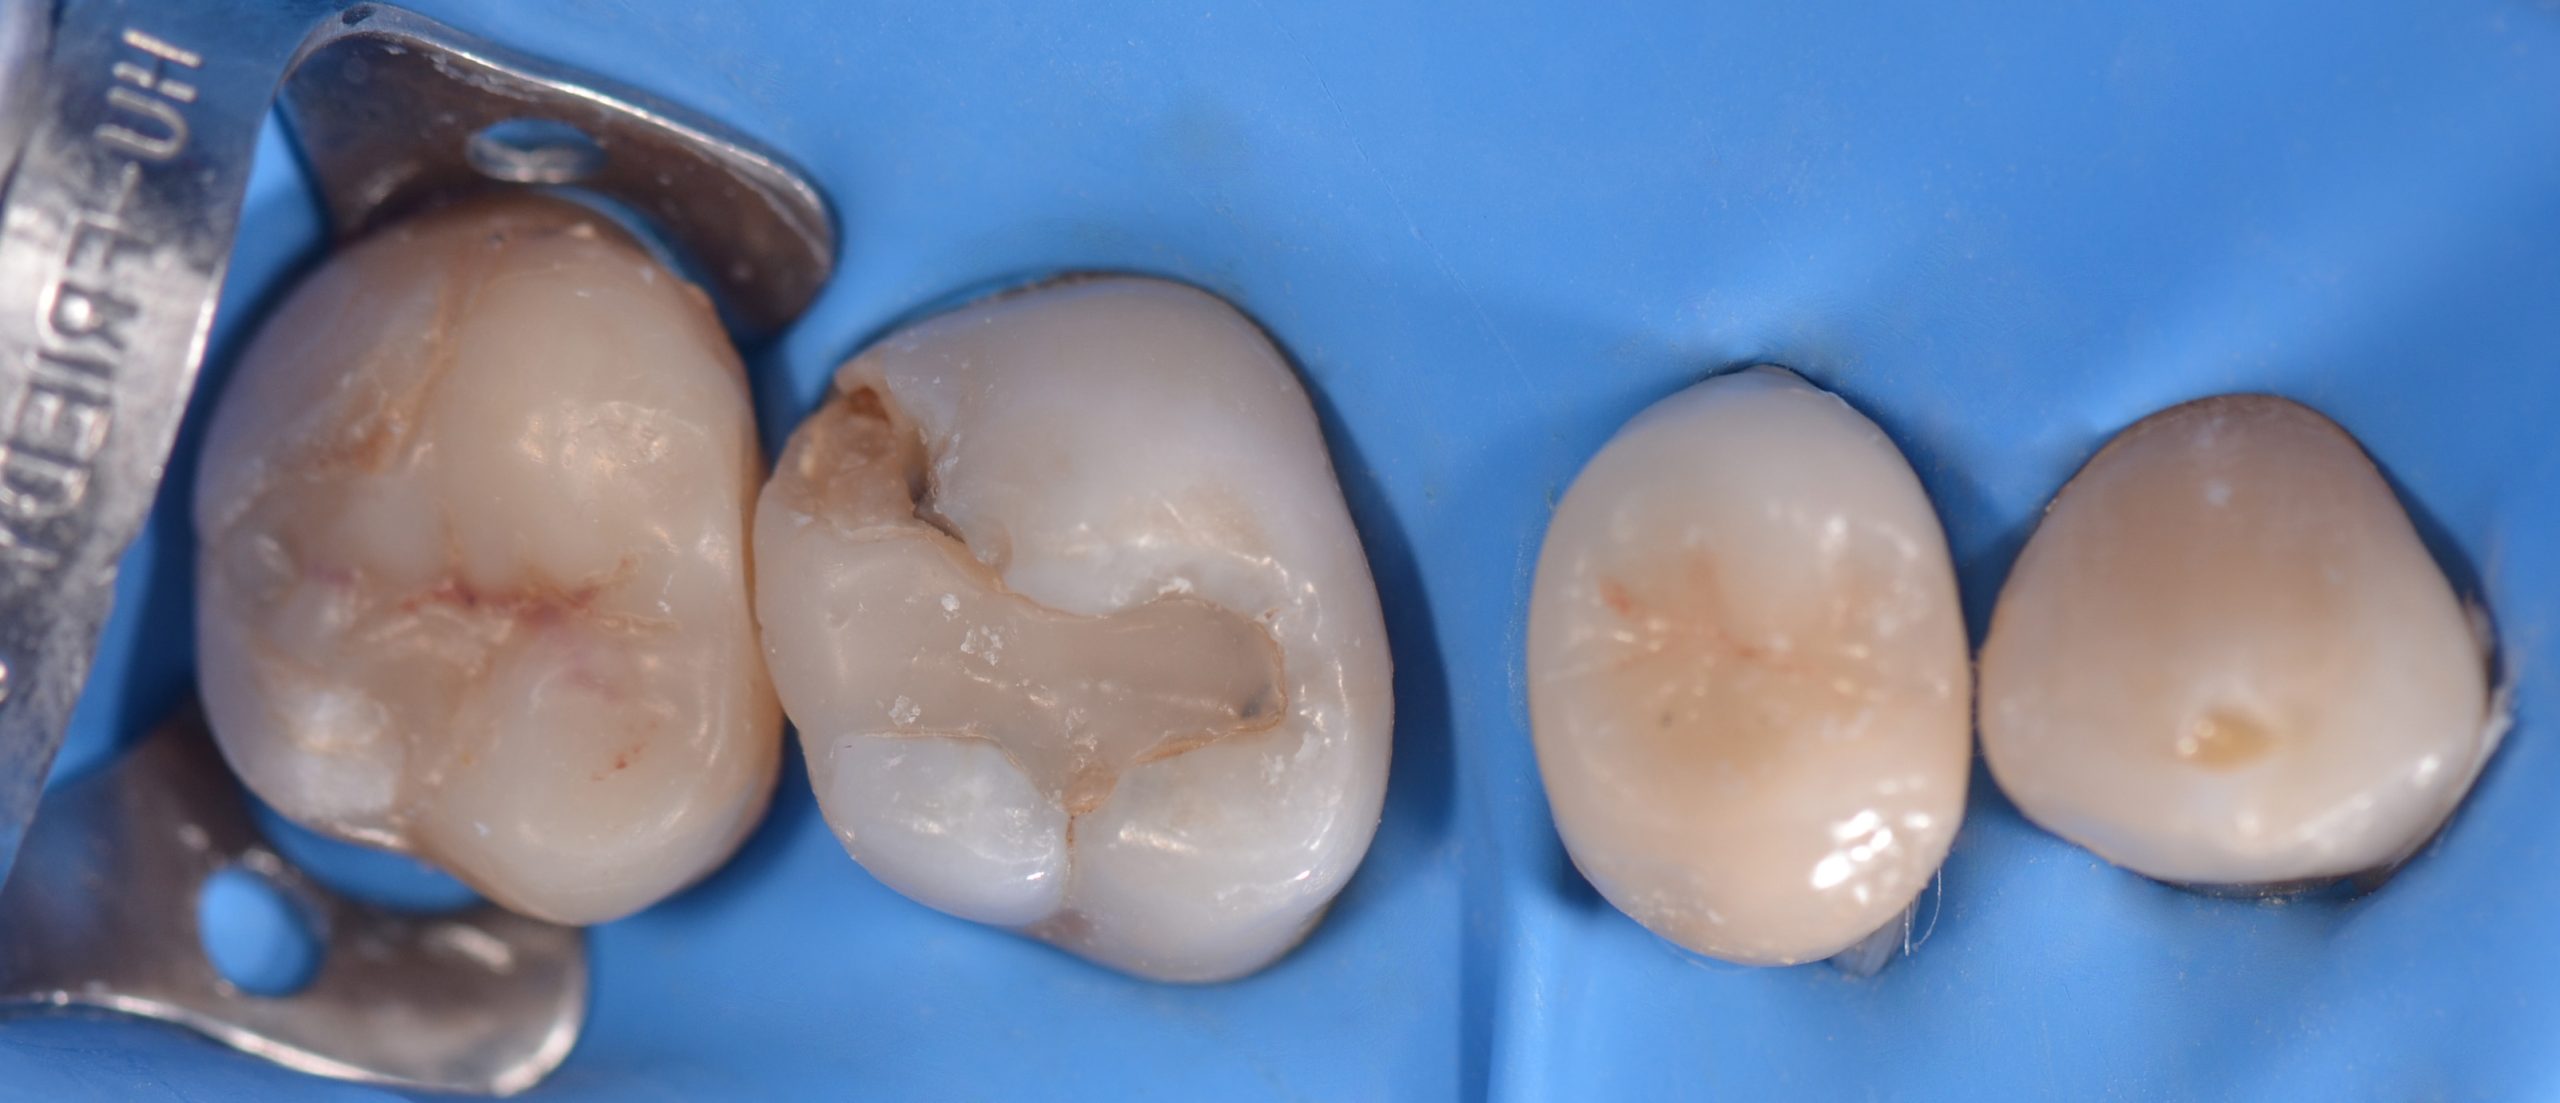

Si esegue anestesia plessica con rinforzo intraligamentoso mediante articaina 1:100.000 sull’elemento 1.6. Successivamente si isola il campo con diga in gomma, utilizzando una clamp 27N sull’elemento 1.7 (Figura 3) con invaginazione del foglio a livello dei colletti.

L’accesso cavitario viene realizzato in modo minimamente invasivo. Per la rimozione del vecchio restauro e l’apertura della cavità si utilizzano:

- fresa diamantata a pallina (gambo lungo, diametro 016);

- fresa cilindrica diamantata a testa arrotondata (corta, diametro 010) seguita da controllo con rivelatore di carie (Figura 4) e verifica degli spessori residui (Figure 5a-b);

- fresa in ossido di zirconio (014) per l’escavazione atraumatica della carie (4) (Figura 6).